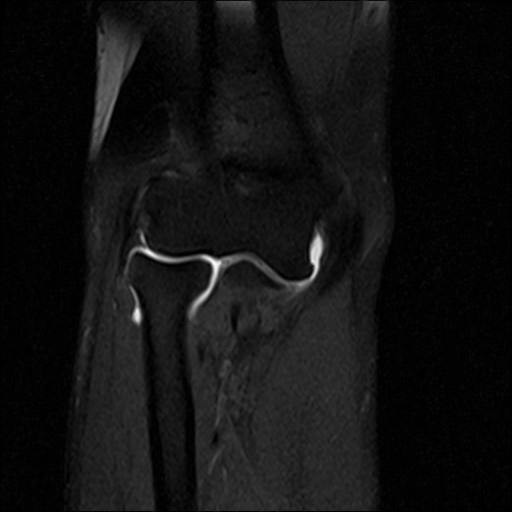

An MRI arthrogram exam is an imaging study. It is used to take detailed pictures of your joints. MRI stands for magnetic resonance imaging. This exam has 2 parts. First you will have an arthrogram and then an MRI. This 2-part exam shows more details of your joint than an MRI by itself. It will help your healthcare provider decide which treatment is best for your medical condition.

- Joints such as knee, hip, and shoulder are made up of 2 bones that fit closely together. Other tissues (cartilage, tendons, and ligaments) support and cushion your joints. An MRI arthrogram helps your doctor see small tears or other problems in these tissues. The results of this exam will help guide your treatment. It will also help your doctor keep track of problems in your joint.